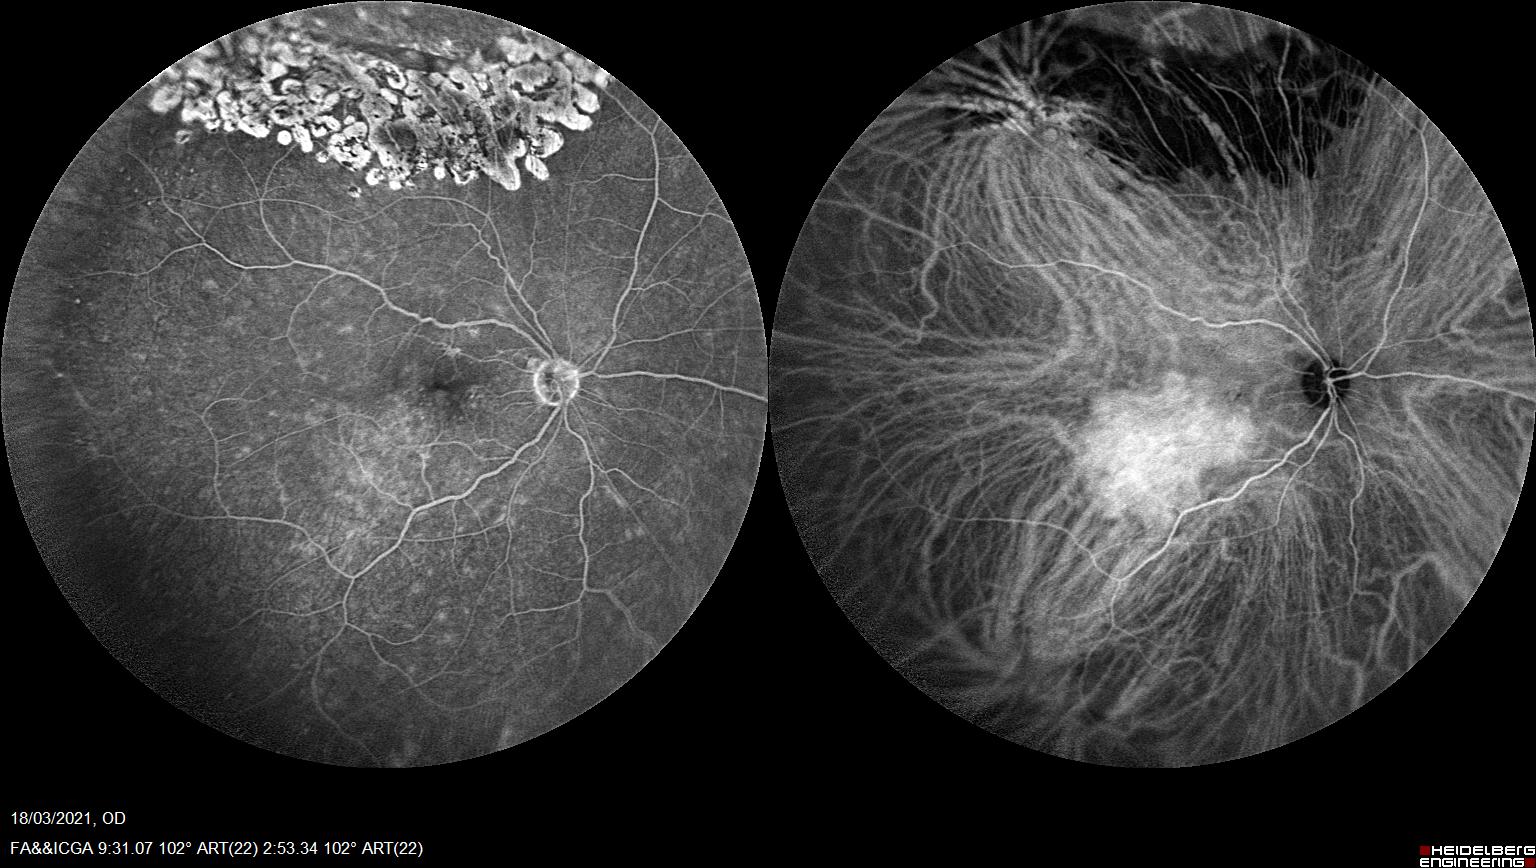

Angiografía fluoresceínica (Imagen de la izquierda) y verde de indocianina (imagen de la derecha) simultáneas en hemangioma coroideo

Una de las herramientas más útiles para su diagnóstico es la angiografía con verde de indocianina.

En la ICV podemos apreciar una hipercianescencia precoz con una iso/hipocianescencia tardía que refleja el alto flujo vascular y capacidad de lavado que presentan estos tumores vasculares a diferencia de otros funduscopicamente similares.